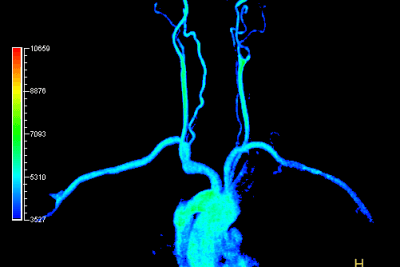

للتصوير أهمية كبيرة في تشخيص أمراض الدماغ وعلاجها ومتابعتها. يوفر الاستخدام الفعال لتكنولوجيا التصوير بالأشعة من حيث التشخيص التفريقي ومراقبة التغيرات التي تحدث أثناء عملية العلاج راحة للأطباء وفائدة كبيرة للمرضى. يعد استخدام تكنولوجيا التصوير بالأجهزة الأكثر تطوراً في أمراض الدماغ أحد الامتيازات المهمة لمؤسستنا.

في مجال الطب النفسي، نحن من أوائل المؤسسات في تركيا التي تطبق تقنيات التصوير بالرنين المغناطيسي المتقدم للدماغ...

مختبر تصوير الدماغ (علم الأعصاب)